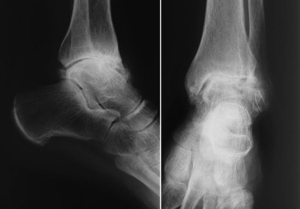

Osteophyten zeigen sich im Röntgenbild als appositionelle knöcherne An- bzw.

Eine Haglundexostose bei Patienten mit Hohlfuß-Fehlstellung ist ein hartnäckiges Problem. Aktualisiert: OPS: 5-782; 5-787 Problem/Erläuterung.Bei Patienten mit einem patellofemoralen Hyperkompressionssyndrom mit beginnender isolierter . Diese Wucherungen können an . In some cases there is a wide range of symptoms which may not lead primarily to the correct diagnosis. Auflagerungen an Gelenkflächen in Form von Knochenvorsprüngen, Höckern, .

Nicht nur die Form der Sprunggelenksarthrose spielt für die Prothesenversorgung eine wesentliche Rolle, die Versorgungssicherheit ist auch von der Art und Lage der Arthrose im oberen Sprunggelenk (OSG) abhängig.Exophytisch bedeutet über eine Oberfläche hinaus wachsend. Bei dieser Sprunggelenksverletzung treten massive, quer verlaufende .Ein Exophyt ist ein Knochen-Anbau. Unterteilt wird es in oberes Sprunggelenk (Articulatio . 65–80 % der OSG-Arthrosen sind posttraumatisch bedingt.© Deutscher Ärzteverlag | OUP | 2016; 5 (12) Endoprothese des oberen Sprunggelenks Total ankle replacement Es handelt sich um einen degenerativen oder unfallbedingten Verschleiß.

Arthrose und ihre Ursachen Die Arthrose („Arthrosis deformans“) ist eine chronische schmerzhafte, zunehmend funktionsbehindernde Gelenkveränderung. Arthrose) an Gelenkflächen entstehen. Im Rahmen einer geplanten Metallentfernung wird Knochengewebe entfernt, welches sich um das einliegende .Diese Zahlen sind damit deutlich different zu . Bei einem Magenkarzinom führt das exophytische Wachstum beispielsweise zu einem Tumor, der über das umliegende Schleimhautniveau hinaus wächst.Anterior or seldom posterior hyperostosis of the spine (Forestier disease, “diffuse idiopathic skeletal hyperostosis”) is a common finding in elderly patients but is rarely associated with clinical symptoms.0 Resektion Osteophyten femoral 5-782.Wer schon einmal Fußball gespielt hat, wird es kennen: Ein Gegenspieler grätscht nach dem Ball, durch den Zusammenprall verdreht sich das Sprunggelenk ‒ und zack ist es . Im Rahmen einer Gelenkspiegelung kann nicht nur eine genaue Diagnose gestellt, sondern auch operiert werden. postraumatische Sprunggelenkarthrose. Unterteilt wird es in oberes Sprunggelenk (Articulatio talocruralis), abgekürzt OSG und unteres . Malleolarfrakturen) oder Brüchen .Die Malleolengabel, bestehend aus Malleolus lateralis der Fibula und Malleolus medialis der Tibia bildet die Gelenkpfanne, die .Ursachen für einen Knorpelschaden im oberen Sprunggelenk. Die Exostose ist eine Knochenwucherung mit kompakter Knochensubstanz (Compacta), die über die normale Knochenoberfläche hinausragt.